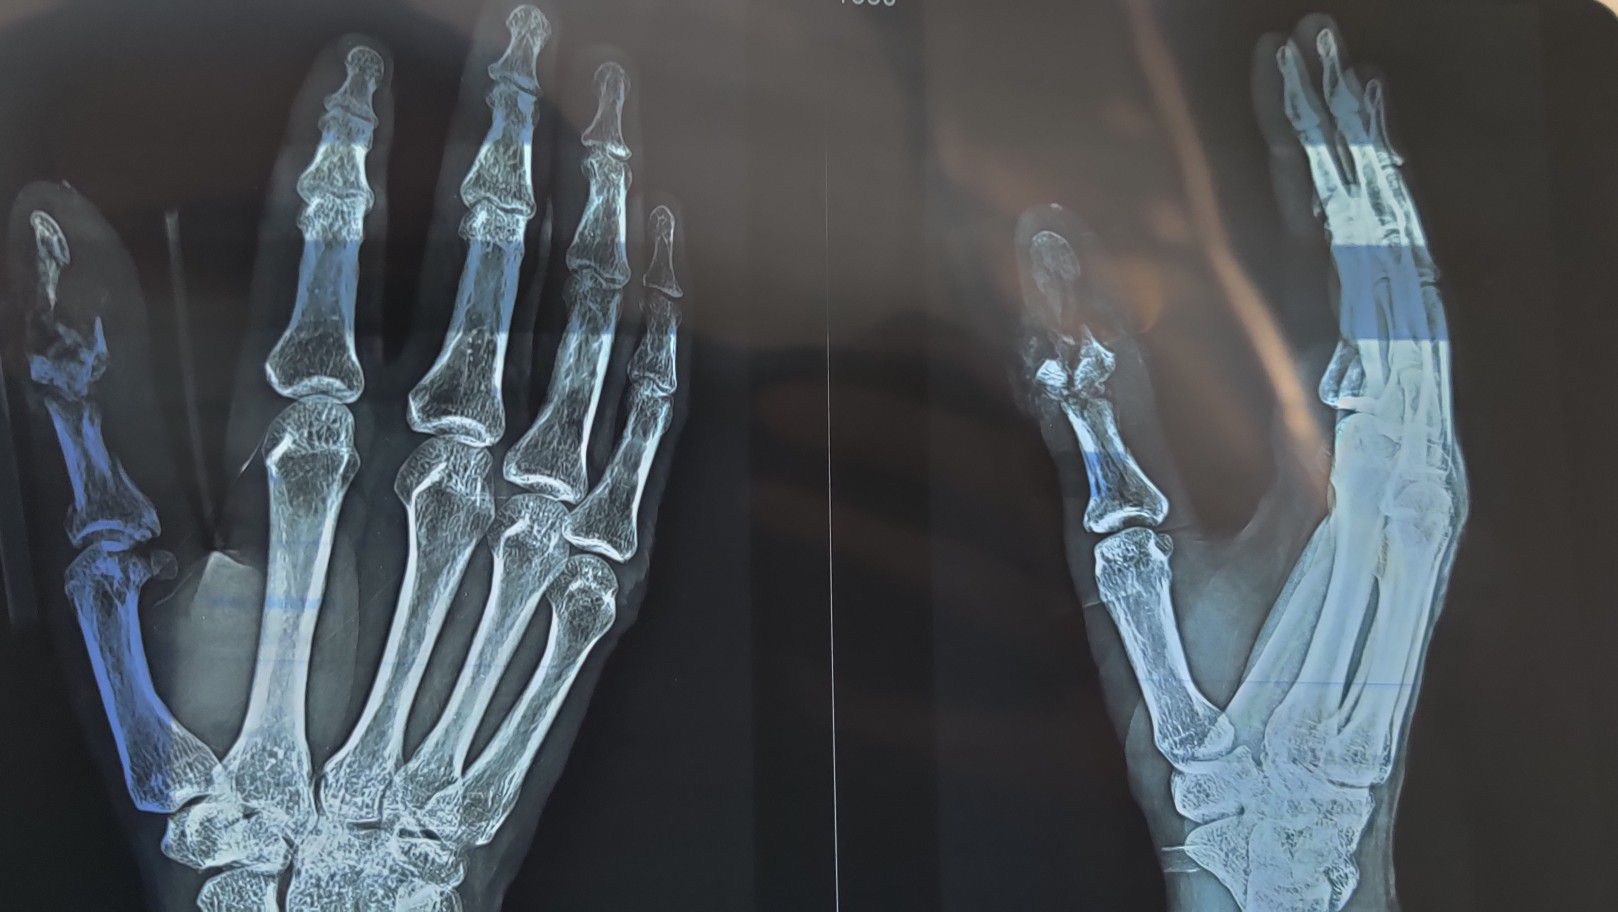

Traumatic Injury to Thumb

Xray

Orthopaedics

Thumb